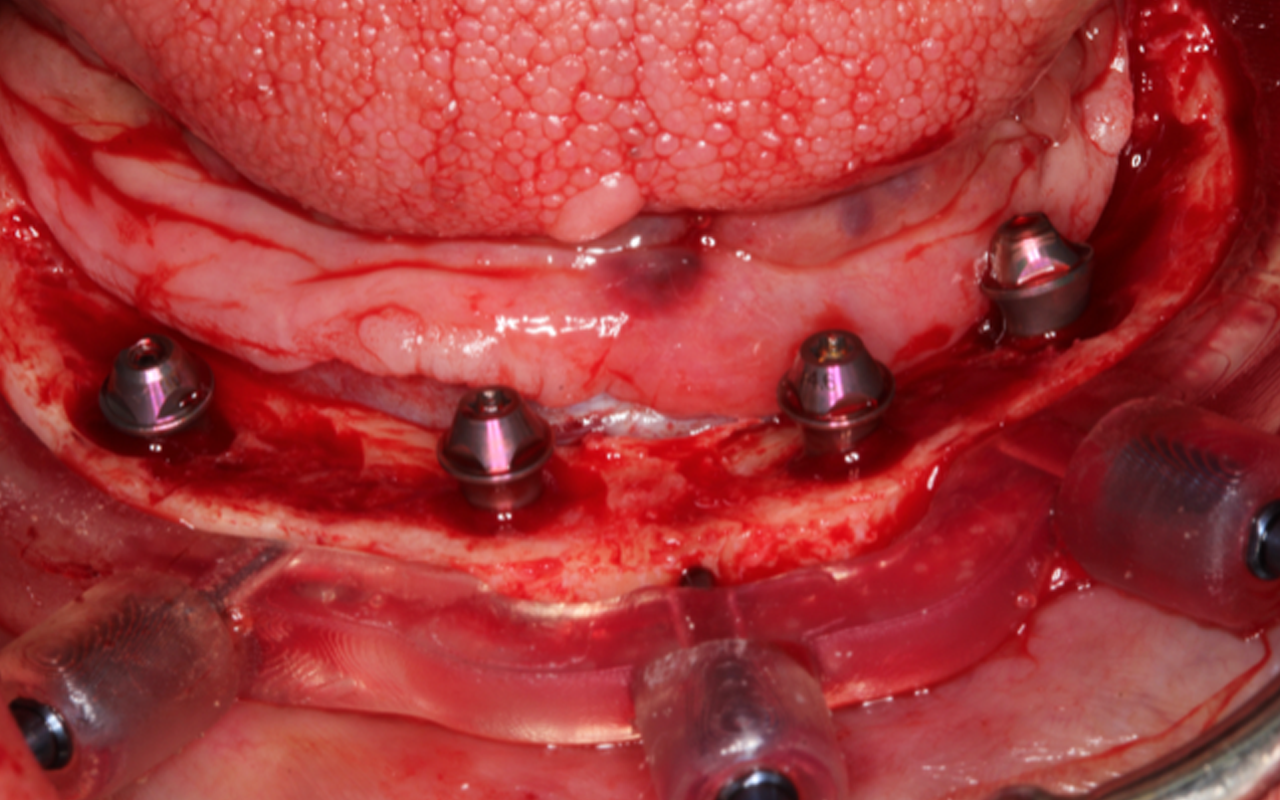

2) Full-arch straight and tilted implant placement and restoration in special plastic models

Full arch patient surgery with 3D surgical and stackable guides, implant scanning protocols with 3Shape and photogrammetry with PIC scanner and the delivery of a 3D printed full arch provisionals.